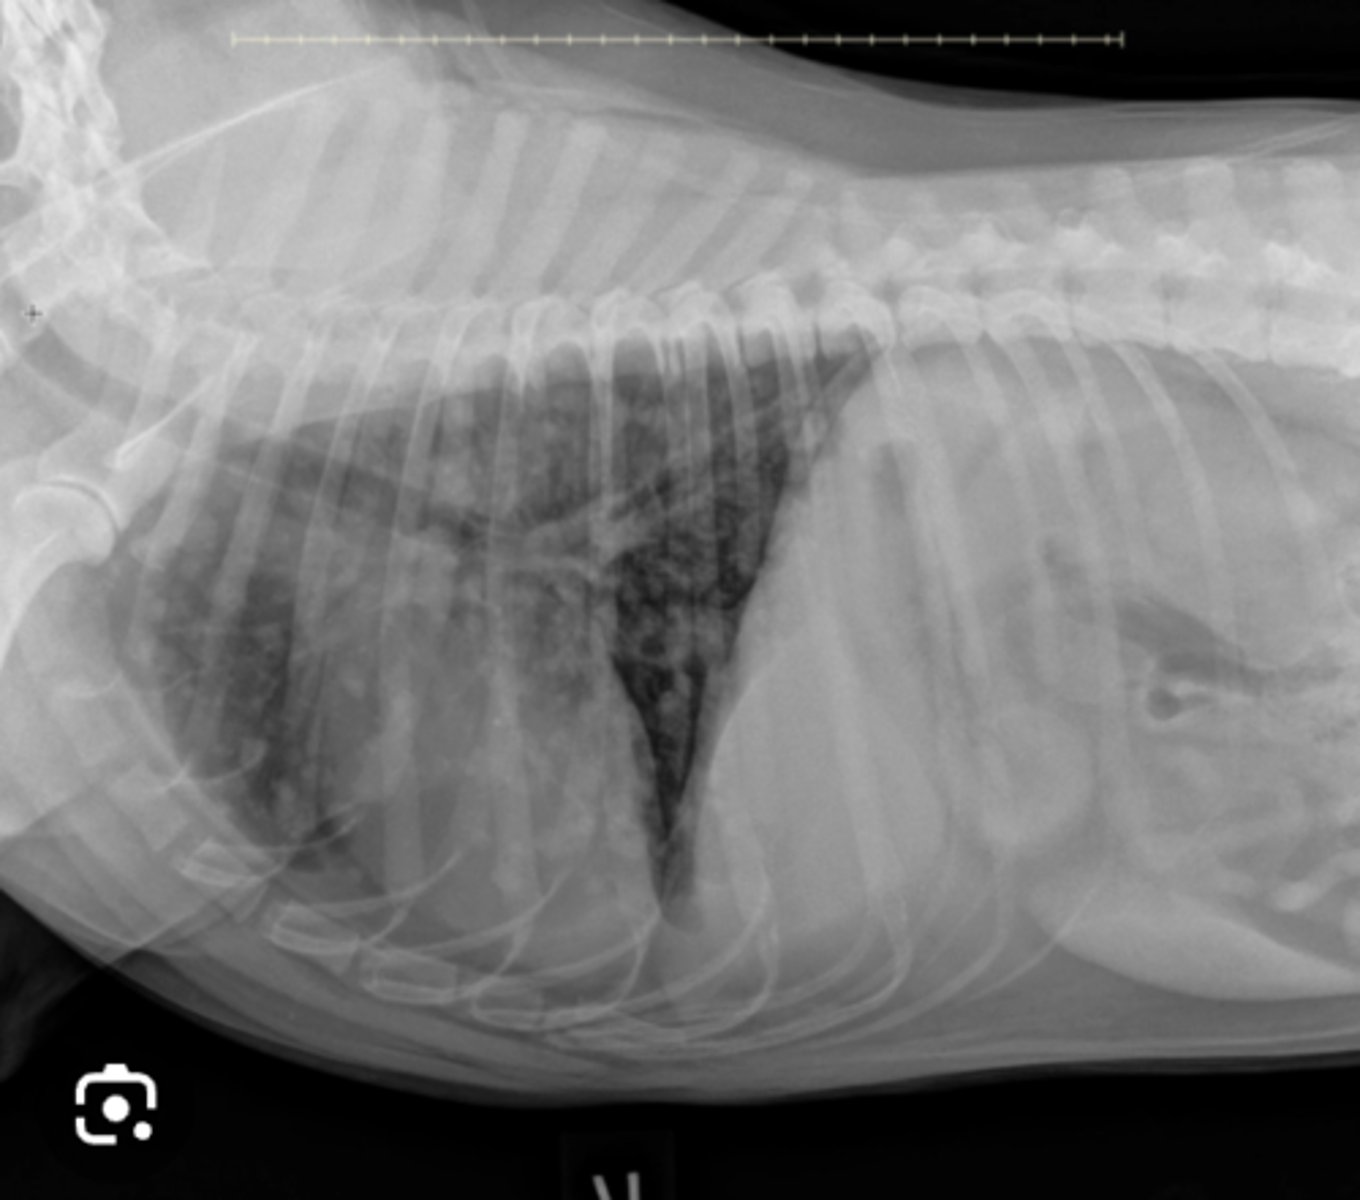

Use this image with this question "Rocky', a 4-year-old Gordon Setter, is presented with a rapid onset of dyspnea. Lung sounds are decreased. The owner is not much help but says "Rocky' was fine yesterday. Only one radiographic view is available, because the patient is distressed. What is your diagnosis based on this lateral radiograph?

Pleural effusion